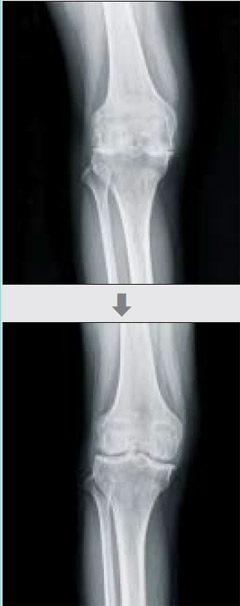

수술 전후 무릎 연골 관절 엑스레이 사진.

카티스템 줄기세포 치료 임상시험 결과 97.7%의 환자에게서 연골이 재생되는 효과가 있었고, 3년 동안 진행된 추적 관찰에서 무릎 통증, 기능성, 활동성, 골관절염 호전도에서 미세골절술(연골에 미세한 구멍을 수십개 뚫어 연골이 채워지게 하는 치료법)을 받은 사람보다 3배 정도 효과가 좋았다. 지난 8월 광주에서 열린 아시아세포치료학회에서 서울제이에스병원 의료진은 줄기세포 수술을 받은 환자 87명을 1년 동안 추적 관찰한 결과를 발표했다. 이들의 평균 나이는 41.77세로, 퇴행성관절염의 기존 치료법인 인공관절 수술을 받기에는 다소 젊은 나이였다. 환자 모두 두께가 1㎜도 남지 않았던 연골이 정상 수준인 5~7㎜로 자랐다〈사진〉. 송 병원장은 내년 여름 세계적인 학회지에 그동안의 수술결과를 발표할 예정이다.